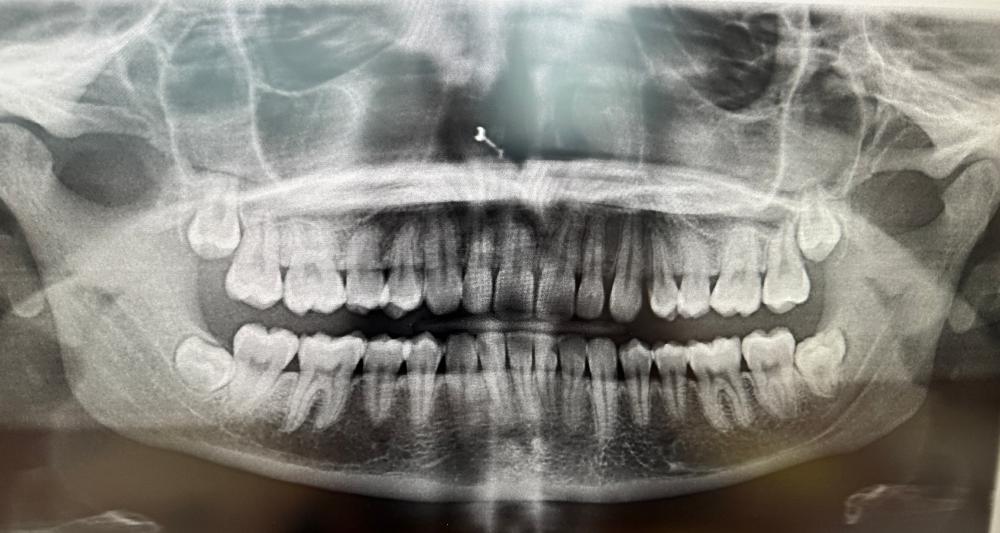

Below are examples of a few sets of surgeries that we routinely perform: